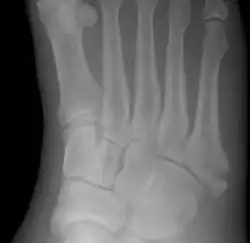

![]() | |

| Jones fracture as seen on Xray | |

Diagnostic X-rays include anteroposterior, oblique, and lateral views and should be made with the foot in full flexion.